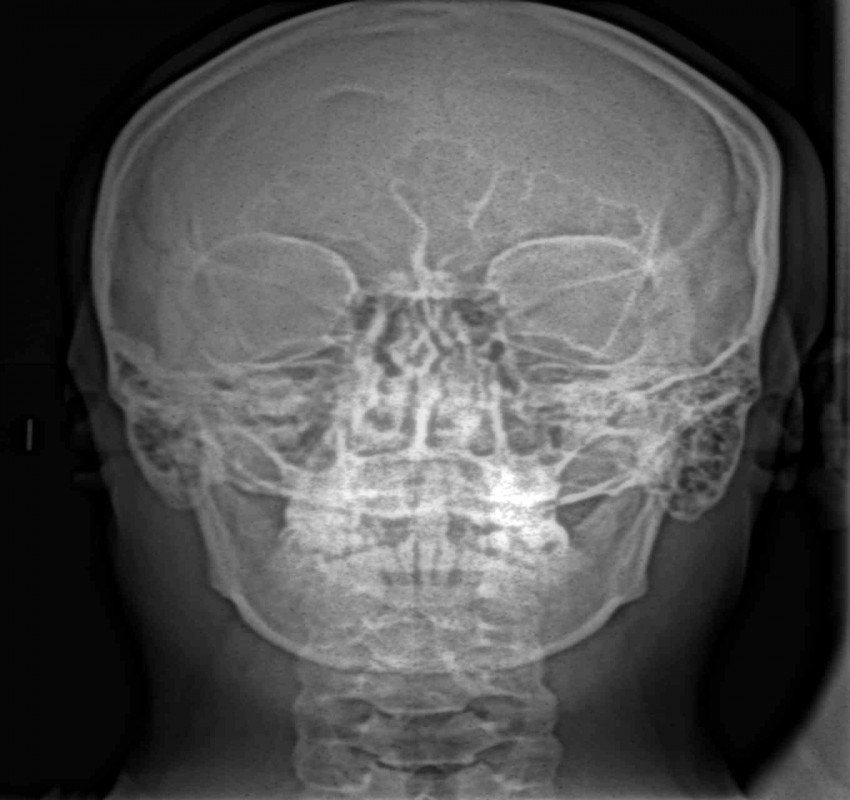

Dentistry has witnessed tremendous advances in all its branches over the past three decades. With these advances, the need for more precise diagnostic tools specially imaging methods has become mandatory. From the simple intraoral periapical x-rays, advanced imaging techniques like computed tomography, cone beam computed tomography, magnetic resonance imaging and ultrasound have also found their place in modern dentistry.

Changes from analouge to digital radiography has not only made the process simpler and faster but also made image storage and manipulation and retrieval easier. The 3- D imaging has made the complex craniofacial structures more accessible for examination.